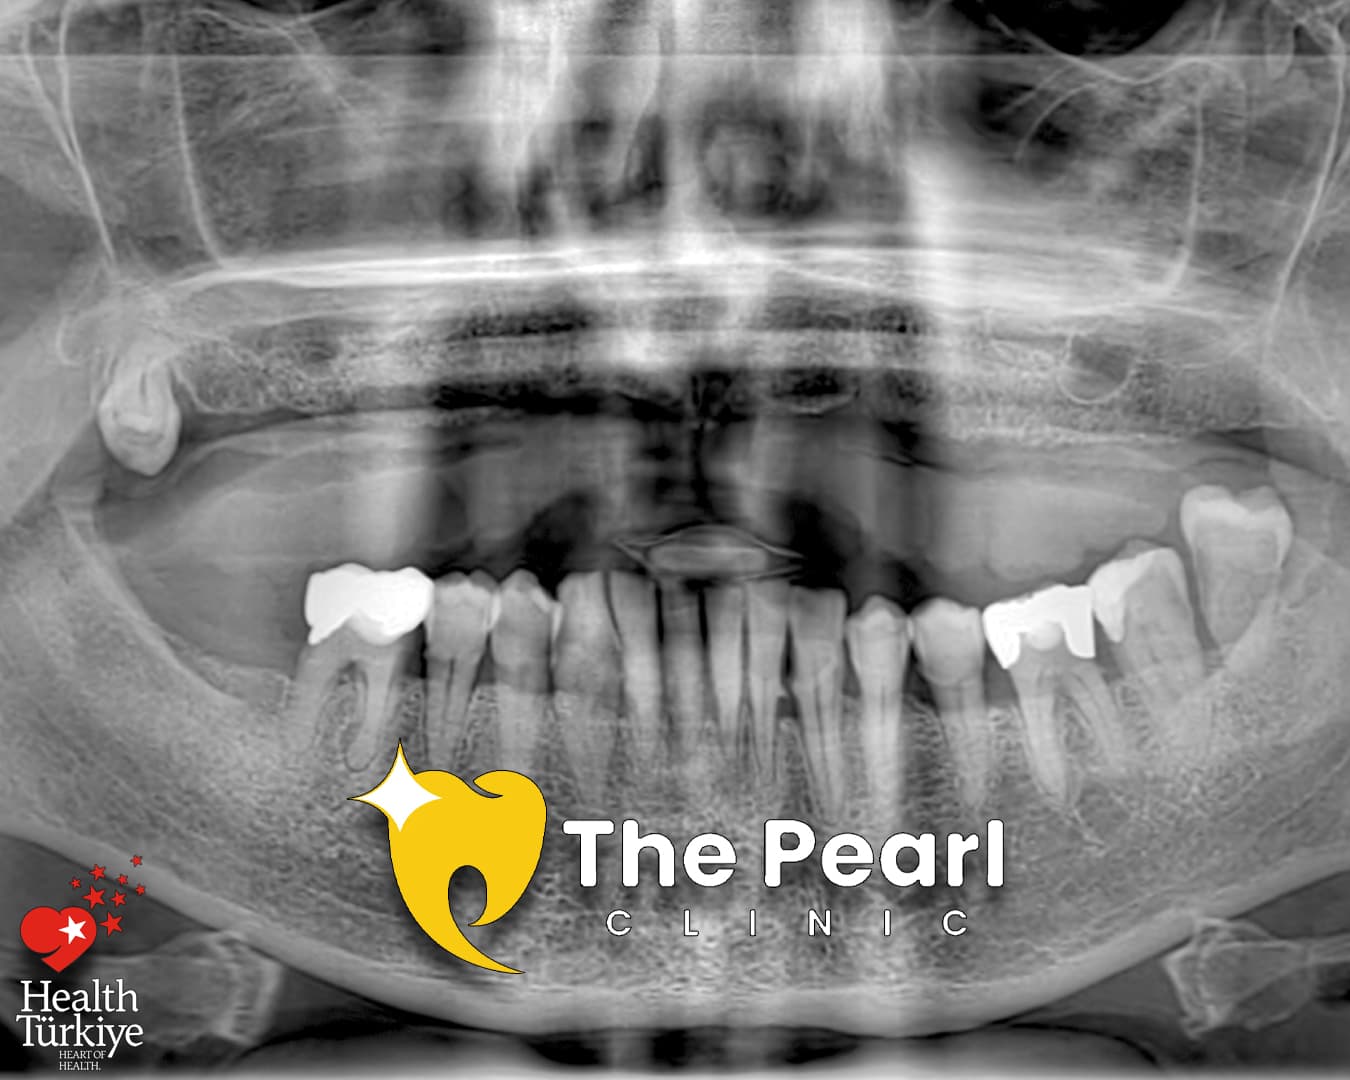

Всё на 6 имплантатах

A successful dental transformation is more than just technical precision; it is about finding the perfect balance between stability and individual expression. This All-on-6 case from our Antalya clinic showcases a Natural Style approach, designed for a patient seeking a seamless and authentic look.